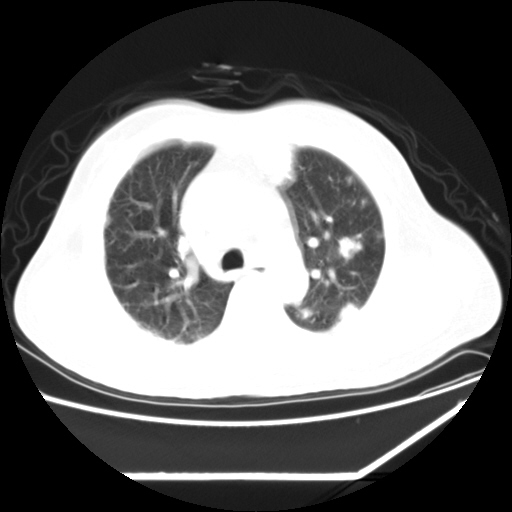

男,57,畏寒,发热

两肺野多发大小不一高密度灶,纵膈内见肿大淋巴结,要考虑转移瘤可能。双侧胸腔少量积液。

双肺多发结节样病灶,部分内见透光区,纵隔内见淋巴结肿大。结核临床如有畏寒,高热,白细胞增高首先考虑迁徙性肺脓肿(多是金黄色葡萄球菌感染)。

注意除外转移瘤。